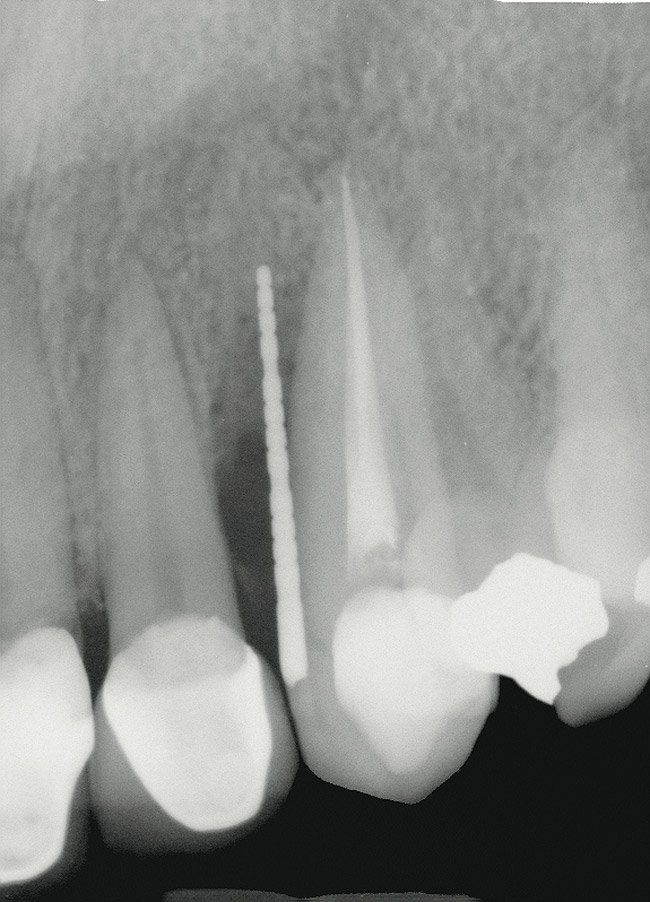

Figure 2  Periapical radiograph of lateral incisor shows periradicular radiolucency but suggests normal interdental bone levels.

Figure 2

A 34-year-old woman presented with a chief complaint of mild discomfort and swelling associated with the maxillary left lateral incisor. The patient reported a history of root canal therapy and crown performed approximately 10 years earlier. Findings from the clinical examination revealed a localized buccal gingival swelling at the level of the mucogingival junction distal to the lateral incisor, with a 9-mm probing depth on the direct facial of the tooth (Figure 1 ). Observations from the radiographic examination demonstrated a periradicular radiolucency but suggested normal interdental bone levels (Figure 2 ). Surgical exposure following flap elevation exposed a 10-mm dehiscence defect of the buccal plate (Figure 3 ), which was consistent with a vertical root fracture and hopeless prognosis. The lateral incisor was extracted to minimize the loss of alveolar bone and this was followed by thorough degranulation of the socket. Particulate FDBA saturated with rhPDGF-BB for 10 minutes was then applied to augment the deficient ridge in preparation for future implant placement (Figure 4 ). The extraction site was developed to approximate the contours of the adjacent alveolar ridge. Then, a resorbable collagen membrane (Bio-Gide®, Osteohealth) was placed over the graft to facilitate graft containment and maintenance of desired alveolar contours (Figure 5 ). Placement of the membrane without disruption or displacement of the graft during completion of the surgical procedure and suturing is critical to ensure clot formation that will support bone formation.